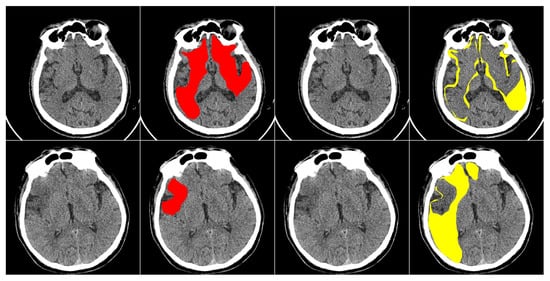

This study primarily focuses on enhancing the performance of multiclass segmentation in brain CT images. The input image is segmented into three regions: ischemic core, penumbra area, and background. The segmentation model produces three output masks, each corresponding to a specific region, with the label “1” representing a significant region and “0” otherwise (Figure 1).

The dataset contains anonymous CT scan results from 112 patients who were hospitalized during the acute phase of ultra-early ischemic stroke within 24 h of the onset of the first symptoms. It includes three classes of labeled regions: ischemic core, penumbra, and background. The images were annotated by an experienced radiologist, who outlined the penumbra and core regions on each relevant slice. In total, the dataset includes 10,165 images, with 8376 slices used as the training set, 980 images reserved for validation (hyperparameter tuning), and 809 slices used for testing. Each image in the dataset has a resolution of 512 × 512 pixels. An example of images from the dataset is shown in Figure 5.